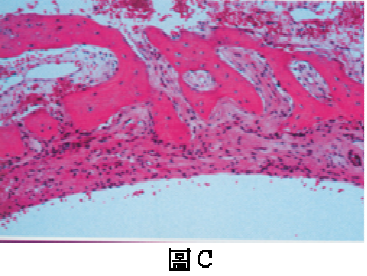

76. 一位16歲男孩在常規X光檢查時,發現左下顎臼齒下方有一放射線透性影像,牙根之間呈現扇形(scalloped),病灶下緣周界較不 清晰(圖A),根尖片可見到清晰之齒槽骨板(lamina dura)(圖B),患處牙齒之牙髓均呈活性反應,口外醫師安排活體切片檢查 時發現放射線透性(radiolucent)病灶內空無一物,刮取病灶周邊組織鏡檢(圖C),可見鄰近之骨組織有一薄層含血管之結締組 織,並沒有發現任何上皮襯底(epithelial lining)。您認為下列何者較符合上述之診斷?

(A)動脈瘤性骨囊腫(aneurysmal bone cyst) (B)史塔尼氏囊腫(Stafne bone cyst) (C)單純性骨囊腫(simple bone cyst) (D)齒源性角化囊腫(odontogenic keratocyst)